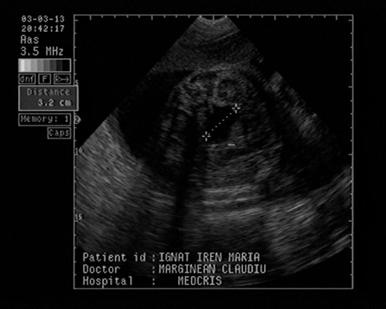

Fig. nr. 268. Formatiune anecogena abdominala fetala independenta de rinichi, la 28 sapt,ulterior in crestere la copilul de 3 ani

Fig. nr. 269. La peste 3 ani de la diagnosticul intrauterin, formatiunea tumorala abdominala ajunge la dimensiunea de 12 cm diametru si cu o structura inomogena cu mici hiperecogenitati sugestive ptr un teratom